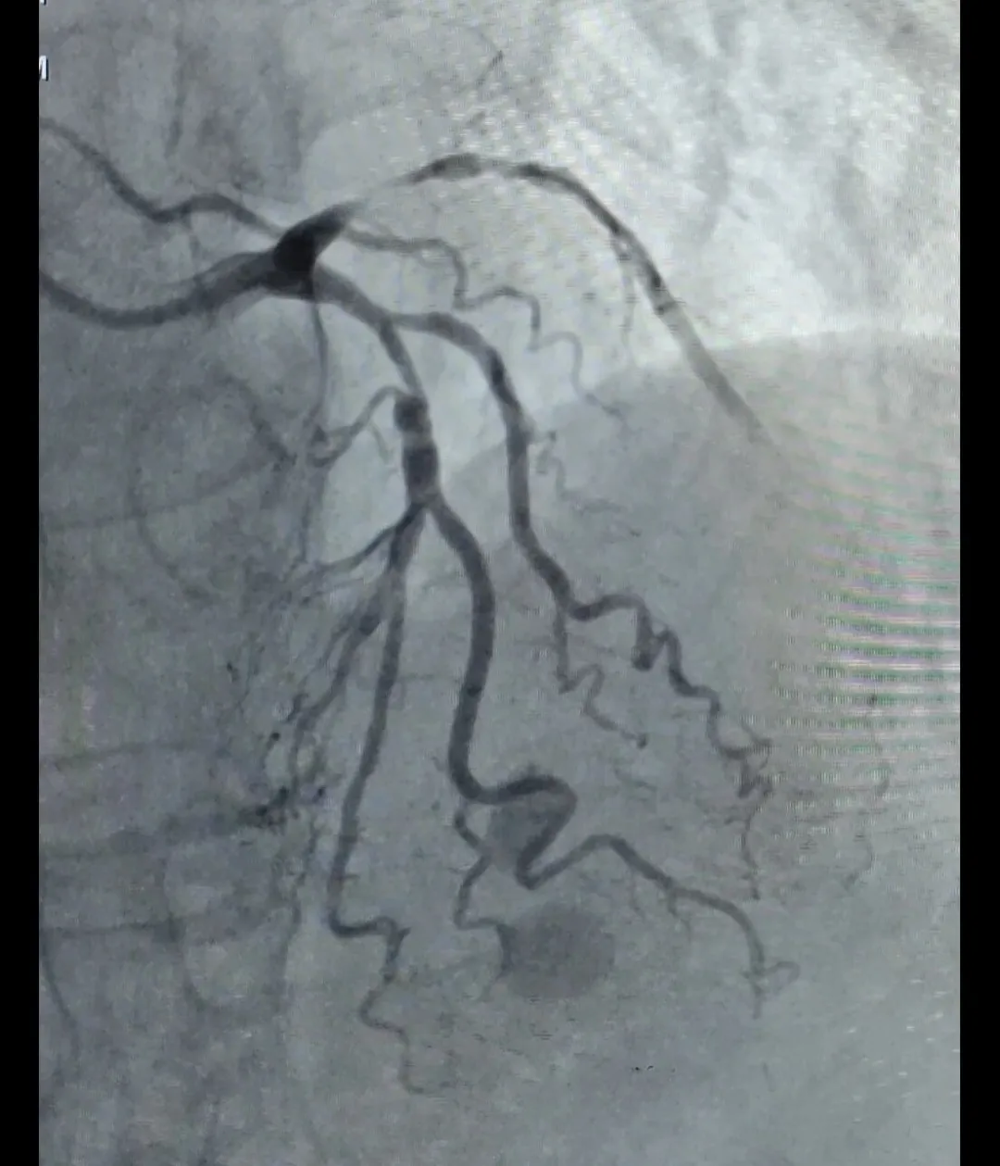

手术前